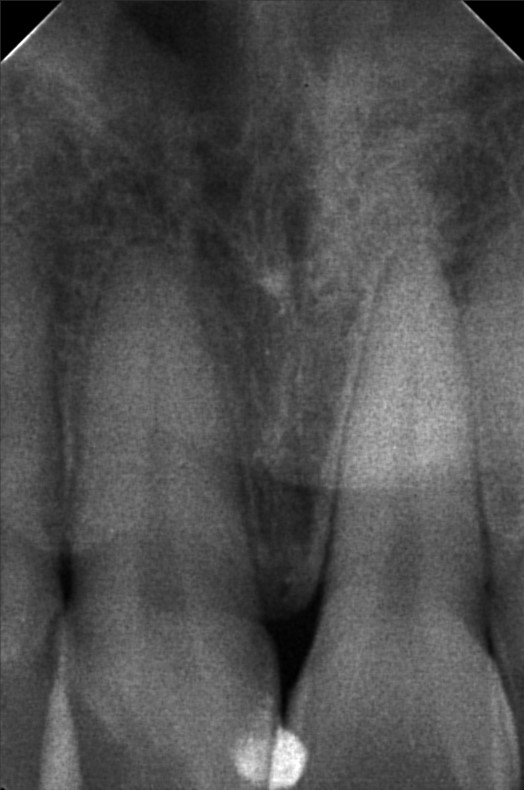

Edit Record Check our patient data records. Add patient information Patient Info Profile picture Last Name First Name Middle Name Birthdate Age Street Barangay City Country Zip Code Contact number Email Procedure 06/30/23- Informed Consent Ortho Check Up OP Impression Soft tissue analysis Intraoral photograph PA Radiograph For exo #15 Informed pt regarding class 5 cases Referred for cephalometric radiograph For resto class 5 #23, #24, #25, #35, #13, #14 10/24/25 oral prophylaxis xray tooth extraction #15 for restoration: abrasion: #23, 24, 25, 26, 14, 33, 35, 36, 44 recession: #13, 12, 11, 21, 22, 34, 32, 43 File atecotech2i712f_f.jpeg File 2 atecotech2i18f6_f.jpeg File 3 atecotech2i2a08_f.jpeg File 4 atecotech2i6330_f.jpeg File 5 atecotech2i278f_f.jpeg File 6 atecotech2i5dba_f.jpeg File 7 File 8 File 9 File 10 File 11 File 12 File 13 File 14 File 15 File 16 File 17 File 18 File 19 File 20 Retain Record Retain Record Yes No Save Your Changes